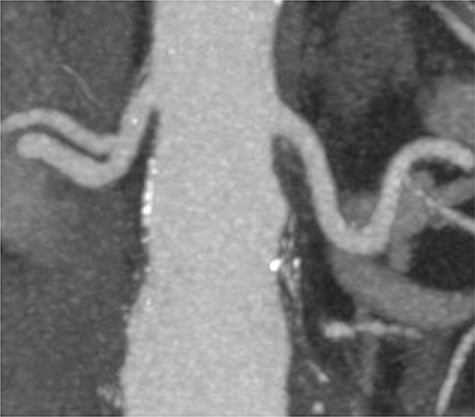

A 78-year-old gentleman admitted for elective FEVAR to treat his CT confirmed 5.7 cm juxtarenal AAA. He was not suitable for open repair and initially offered the option of no intervention due to ongoing comorbidities resulting in poor cardiopulmonary function; however, he was keen to proceed with surgery. From pre-implant planning CT angiogram (CTA), infrarenal endograft was unsuitable for EVAR due to reverse conicity and unhealthy infrarenal aortic neck (Fig. 1); therefore, FEVAR was chosen. RRHA from SMA was also seen in pre-operative CTA but not reported (Fig. 2).

Pre-implant planning CTA showing unhealthy infrarenal aortic neck.

Pre-operative CTA showing healthy SMA (arrowhead) with RRHA (arrow).